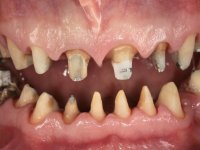

Paciente do sexo masculino, com 42 anos de idade, não fumador. Apresentava uma reabilitação metalo -cerâmica feita há mais de 10 anos com exposições radiculares e infiltrações. No maxilar superior apresentava uma coroa no 1.1,uma ponte de dois elementos no 2.1 e 2.2.e uma ponte de 4 elementos nos dentes 2.4,2.5,2.6 e 2.7 com o 2.6 como pôntico. Os dentes 1.6/1.5/1.4/1.3/1.2/1.1/2.1/2.2/2.3/2.4/2.5 e 2.7 apresentam tratamento endodôntico radical com o 2.4/2.5 e 2.7 a necessitarem de ser refeitos. No maxilar inferior apresentava uma ponte metalo-cerâmica de 4 elementos nos 4 incisivos e uma ponte de 3 elementos (3.3 e 3.4) com um dente supranumerário como pôntico. Os dentes 4.6/4.5 e 4.2 apresentavam tratamento endodôntico com o 4.2 a necessitar de ser refeito. Os dentes 4.3 e 4.4 apresentavam extensas cáries linguais com algum comprometimento mesial. As peças protéticas apresentavam-se infiltradas com exposição radicular associada. Apresentava uma D.V.O. diminuída e uma mordida cruzada lado direito. O paciente tinha uma satisfatória saúde periodontal e uma boa higiene oral.

A primeira acção terapêutica foi tentar melhorar o tratamento endodôntico dos dentes (2.4/2.5/4.2)). A sua manutenção em boca seria condicionada pelo sucesso desta intervenção. Seguidamente foram feitas impressões em alginato e registo inter-maxilar em silicone para confeção em laboratório de uma ponte provisória em acrílico com reforço. O objetivo desta ponte provisória seria ensaiar o aumento da D.V.O. e descruzar a mordida do lado direito. Foi utilizado um monobloco de 13 dentes com o dente 2.6 com o pôntico. As coroas e as pontes foram removidas e os remanescentes coronários foram repreparados. A ponte provisória foi rebasada primeiramente com acrílico auto-polimerizável e de seguida com resina composta. Após 2 semanas de permanência em boca, foram feitas as impressões para confeção da ponte provisória inferior também realizada em laboratório. Especial cuidado foi colocado na remoção das coroas antigas, sendo feito primeiramente um corte axial que permitiu que fossem removidas de uma forma menos traumática. A temporização foi feita durante 8 semanas, permitindo que os tecidos gengivais estabilizassem posicionalmente. As impressões definitivas foram realizadas após afastamento gengival utilizando a técnica do fio único impregnado. Foi utilizada a técnica de dupla mistura com dupla viscosidade (putty soft e light).Simultaneamente foi realizada a recolha das relações inter-maxilares e o registo com arco facial. Foram confecçionados os modelos de trabalho e feita a sua correta montagem em articulador semi-ajustável. Em seguida foram feitas infra estruturas em zircónia que posteriormente foram revestidas por cerâmica. A prova de “biscoito” foi realizada em boca para avaliação estética e funcional sendo também avaliado o seu assentamento e ajuste. A reabilitação definitiva foi cimentada em boca utilizando um cimento de ionómero de vidro reforçado por resina.